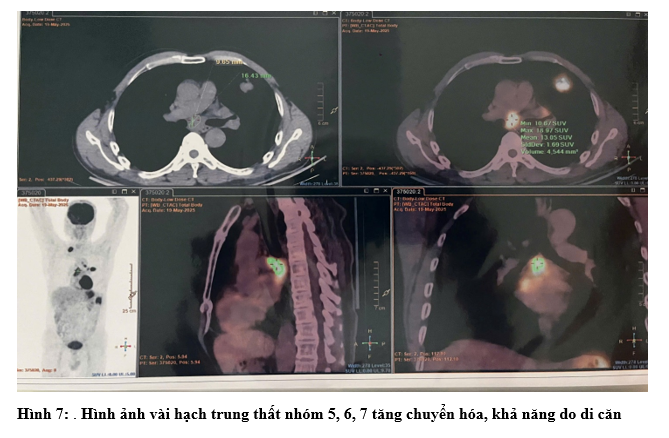

- Chụp Cắt Lớp Vi Tính Ngực: Phổi trái: thùy trên có khối ~ 27x30mm, bờ tua gai.Phổi phải: đỉnh phổi thùy trên có nốt đặc ~ 10mm.Tuyến thượng thận trái có khối ~ 21x32mm.Trung thất vị trí ngã ba khí phế quản và cửa sổ chủ phổi có vài hạch, hạch lớn nhất kích thước 10x13mm

- Chụp PET/CT: Hình ảnh dày thành đại tràng góc lách, dày nhất 18mm, trên đoạn 41mm, tăng chuyển hóa, thâm nhiễm mỡ xung quanh. Vài hạch ở cạnh tổn thương đại tràng, cạnh động mạch chủ bụng và cạnh thân tụy tăng chuyển hóa, khả năng do di căn. Hình ảnh tổn thương bờ tua gai ở S3 phổi trái, kích thước 31x26x22mm, tăng chuyển hóa, khả năng là tổn thương ác tính nguyên phát. Hình ảnh vài hạch trung thất nhóm 5, 6, 7, hạch thượng đòn Phải tăng chuyển hóa, khả năng do di căn. Hình ảnh vài nốt bán đặc và kính mờ rải rác nhu mô phổi 2 bên, có nốt tăng chuyển hóa, khả năng do di căn